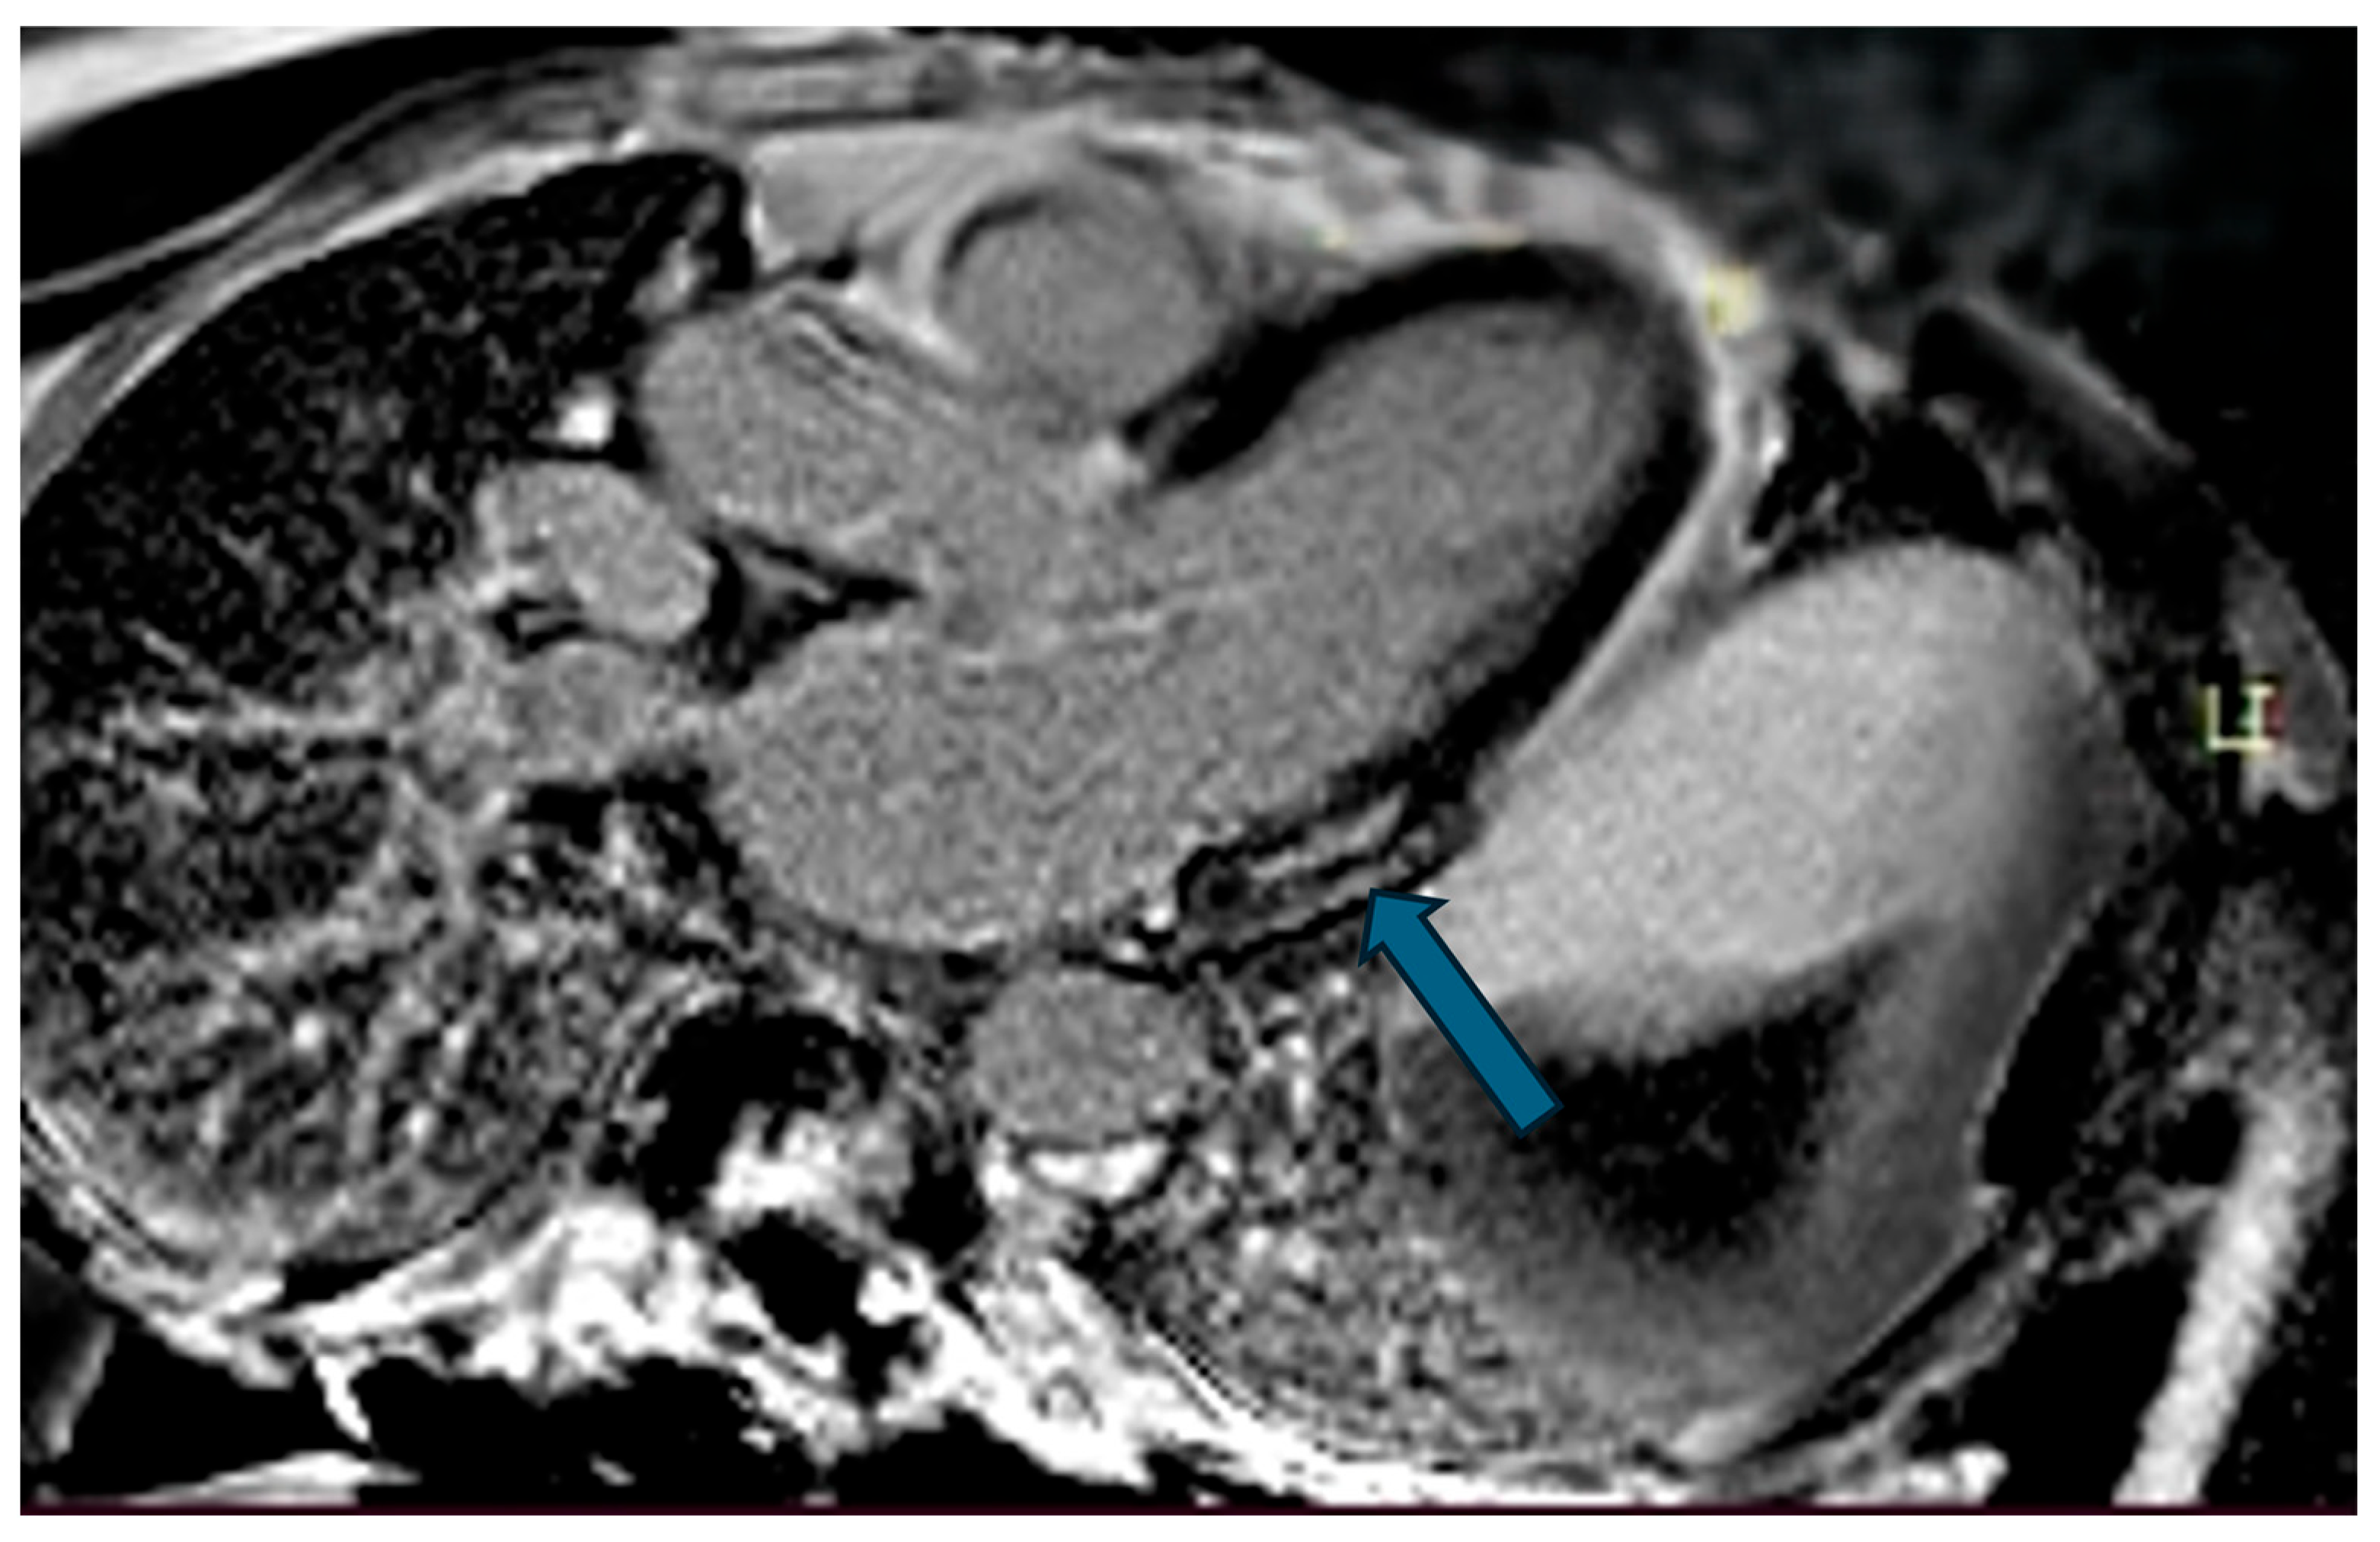

| LGE | Late Gadolinium Enhancement |

| Case | Patient (Sex, Age) | Symptoms | MAD (mm) | Valvular Issues | LGE | Other Details |

|---|---|---|---|---|---|---|

| 7 | Female, 53 years old | Extrasystole and syncope | 15 | MVP, valvular regurgitation | Basal-lateral | Extensive MAD with MVP and LGE; increased arrhythmic risk; antiarrhythmic therapy considered. |

| 8 | Female, 63 years old | Aortic and mitral regurgitation | 11 | Aortic and mitral regurgitation | Lateral | Aorto-mitral regurgitation with septal hypokinesia; mitral valve repair performed; heart failure therapy started. |